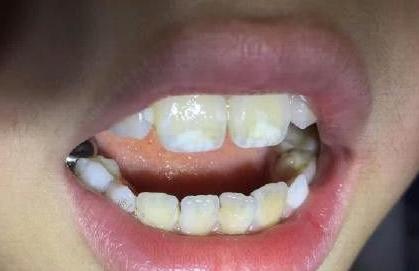

*补牙材料染色:如银汞合金长期与牙齿接触,充填材料会渐渐渗透到牙本质小管引起牙齿变黑或者褐色。

*龋齿:龋齿等牙齿实质性缺损,食物残渣堆积在龋洞内,经产色细菌分解,有色物质进入牙本质,多呈黑绿色。